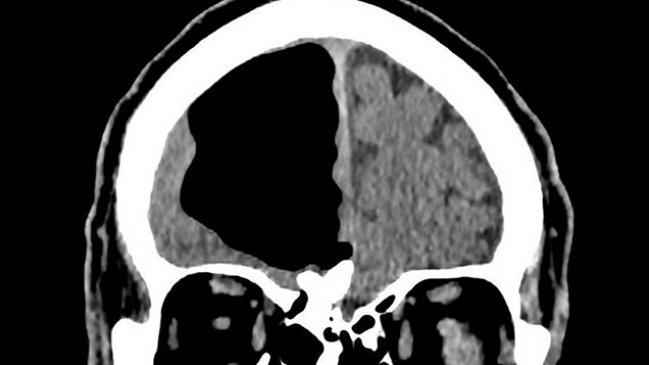

Un hombre de 84 años sorprendió a un grupo de médicos que hallaron un gran hueco de aire en el lugar donde debería ir su cerebro.

Según informó Washington Post, el espacio anormal medía cerca de nueve centímetros y es algo común en pacientes que han tenido cirugía cerebral, aunque en tamaños mucho menores. El fenómeno también podría producirse por infecciones nasales o por golpes faciales.

No fue hasta que le realizaron tomografías cuando notaron el hueco de aire en el lóbulo frontal derecho de su cabeza: una parte de su cerebro estaba desaparecida.

“¡Estábamos todos perplejos por las imágenes! En mi investigación no encontré muchos casos similares a este”, dijo al Washington Post Finlay Brown, médico que estaba trabajando en el hospital que recibió a este hombre.